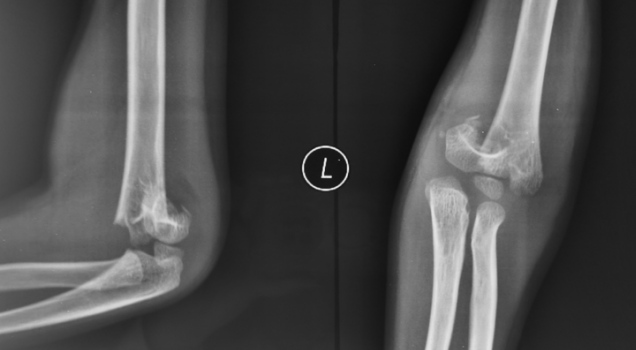

病例1:小明(化名)、男、12岁,8年前因摔伤致“左肱骨髁上骨折”,于外院行手术治疗,手术后逐渐发生左肘内翻畸形。

受伤当时的X线片

手术后X线片

该例患者虽行手术治疗,但从术后X线片上分析其骨折端旋转畸形矫正不充分,残余肱骨远端的内旋畸形,所以术后逐渐发生肘内翻畸形。针对该患者我们实施了手术矫形治疗。